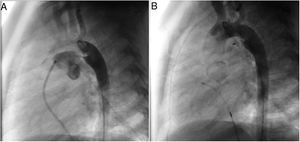

MethodsAll consecutive pediatric patients referred to our center for percutaneous PDA closure from January 2006 until September 2018 were included in this study. Medical record data was collected and reviewed retrospectively. Informed written consent was obtained from the parents or legal guardians. Indications for closure were presence of cardiac murmur, left-sided volume overload detected by non-invasive cardiac imaging, or signs of heart failure. All procedures were performed under general anesthesia. Arterial access was obtained in all patients. An intravenous bolus injection of 100 IU/kg heparin was administered at the start of the procedure. Our endocarditis prophylaxis protocol consisted of cephazolin 25-30 mg/kg every eight hours for 24 hours, and no anti-aggregation was advocated. In every patient, an aortogram was performed in the lateral projection to define the morphology and size of the duct. According to these results, feasibility for percutaneous closure was determined and, when deemed feasible, appropriate devices were selected. At our department, the Nit-Occlud® occlusion device (pfm, Cologne, Germany) has been available since 2006, with the Amplatzer™ duct occluder being implemented in 2011. As standard of care, all devices were preferably deployed anterogradely. A post-implantation aortogram was obtained to check for residual shunts or any anomaly in the device position. All patients were assessed six hours after the procedure for hemodynamic instability and unpalpable distal arterial pulses. The following day, before discharge, the location of the device was noted on a chest radiograph and a transthoracic echocardiography was performed to exclude residual leakage or other complications. Clinical and echocardiographic follow-up assessments were performed at one, three, six and twelve months after the procedure, and annually thereafter.

A coil was used in 139 patients (62.9%) and an Amplatzer duct occluder was used in 79 patients (35.7%). In the three remaining patients (1.4%), an Amplatzer vascular plug was used for closure (Figures 2-8). Despite the higher overall rate of coil device implantation, Amplatzer duct occluder usage had been clearly superior since 2011. Of all coil devices used, 55% were either 4x4 mm or 5x4 mm in size (Figure 9), and of all duct occluder devices used, 72% were Amplatzer duct occluder I 6x4 mm or 8x6 mm in size (Figure 10), which correlates to the fact that most patients who were referred had small- to moderate-sized ductus arteriosus. While ADO II and ADO II AS devices can be implanted in a retrograde fashion, only on two occasions was a retrograde deployment performed (both ADO II devices).

Both patients with history of previous PDA closure were successfully treated. The first was a seven year-old child who had a coil implanted at age three. The procedure was technically difficult, requiring a guidewire capture using a snare catheter to go through the residual PDA (Figure 11), and an Amplatzer duct occluder II 3x4 mm device was implanted successfully. The second patient was a 19 month-old child with PDA and pulmonary hypertension after an unsuccessful surgical ligation. In this case, sizing with a Tyshak balloon was required before implanting an Amplatzer duct occluder II 3x4 mm device (Figure 12).